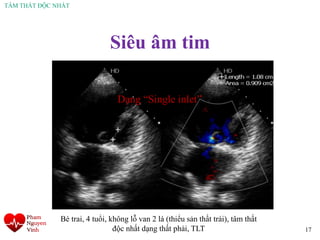

17

Bé trai, 4 tuổi, không lỗ van 2 lá (thiểu sản thất trái), tâm thất

độc nhất dạng thất phải, TLT

Dạng “Single inlet”